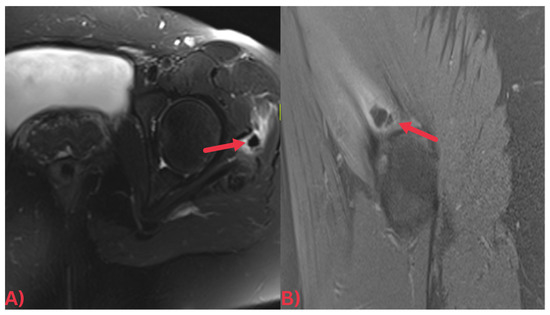

Specifically, MRI images display hydroxyapatite deposits as regions with low signal intensity across both T1- and T2-weighted images, attributable to the high mineral content of hydroxyapatite, a form of calcium phosphate crystals [27]. Consequently, this results in its manifestation in MRI images (Figure 3). Concurrently, MRI also reveals inflammation signs within surrounding soft tissues, such as edema and increased signal intensity on T2-weighted images [28] (Figure 4). Edema, a common response to inflammation or injury, indicates the body’s reparative efforts, while a heightened signal intensity on T2-weighted images typifies inflammation and is present in several conditions, including HADD (Figure 5).

Figure 3. (A) Axial T2 fat-saturated MRI image and (B) sagittal PD fat-saturated MRI image of the left hip demonstrating a well-defined low signal intensity calcification at the insertion of the left gluteus medius tendon (red arrows) with surrounding soft tissue edema.